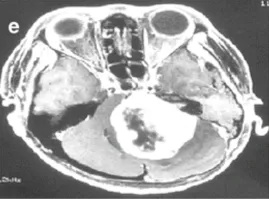

下图显示了放射治疗失败的其他病例,与这些患者相比,这些患者表现出更快的肿瘤再生长和更严重的临床症状(图3a–c)。由于脑干受压增加,这些病例都需要在伽玛刀治疗后3年内进行显微手术切除。图3d–f展示了立体定向放射治疗(SRT)之后的一些放射学变化。

e-36岁女性。增强后轴向磁共振成像显示左侧较大肿瘤,在不适当的三次伽马刀治疗后明显压迫脑干。